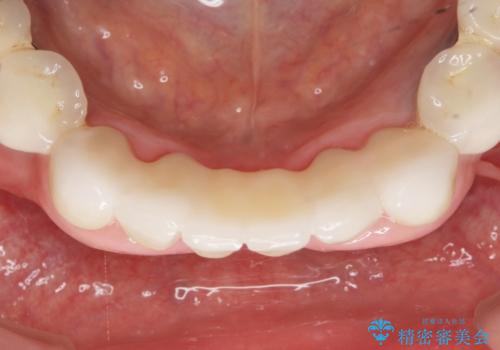

抜歯後歯肉の治癒を十分に待ったのち、ブリッジによる補綴治療を行いました。

- ¥1,010,000 (仮歯×9本、ファイバーコア×1本、ジルコニアクラウン スタンダード×9本)費用は治療当時の料金となります

自然な仕上がりと使い心地に喜んで頂けました。

ジルコニアクラウン スタンダード